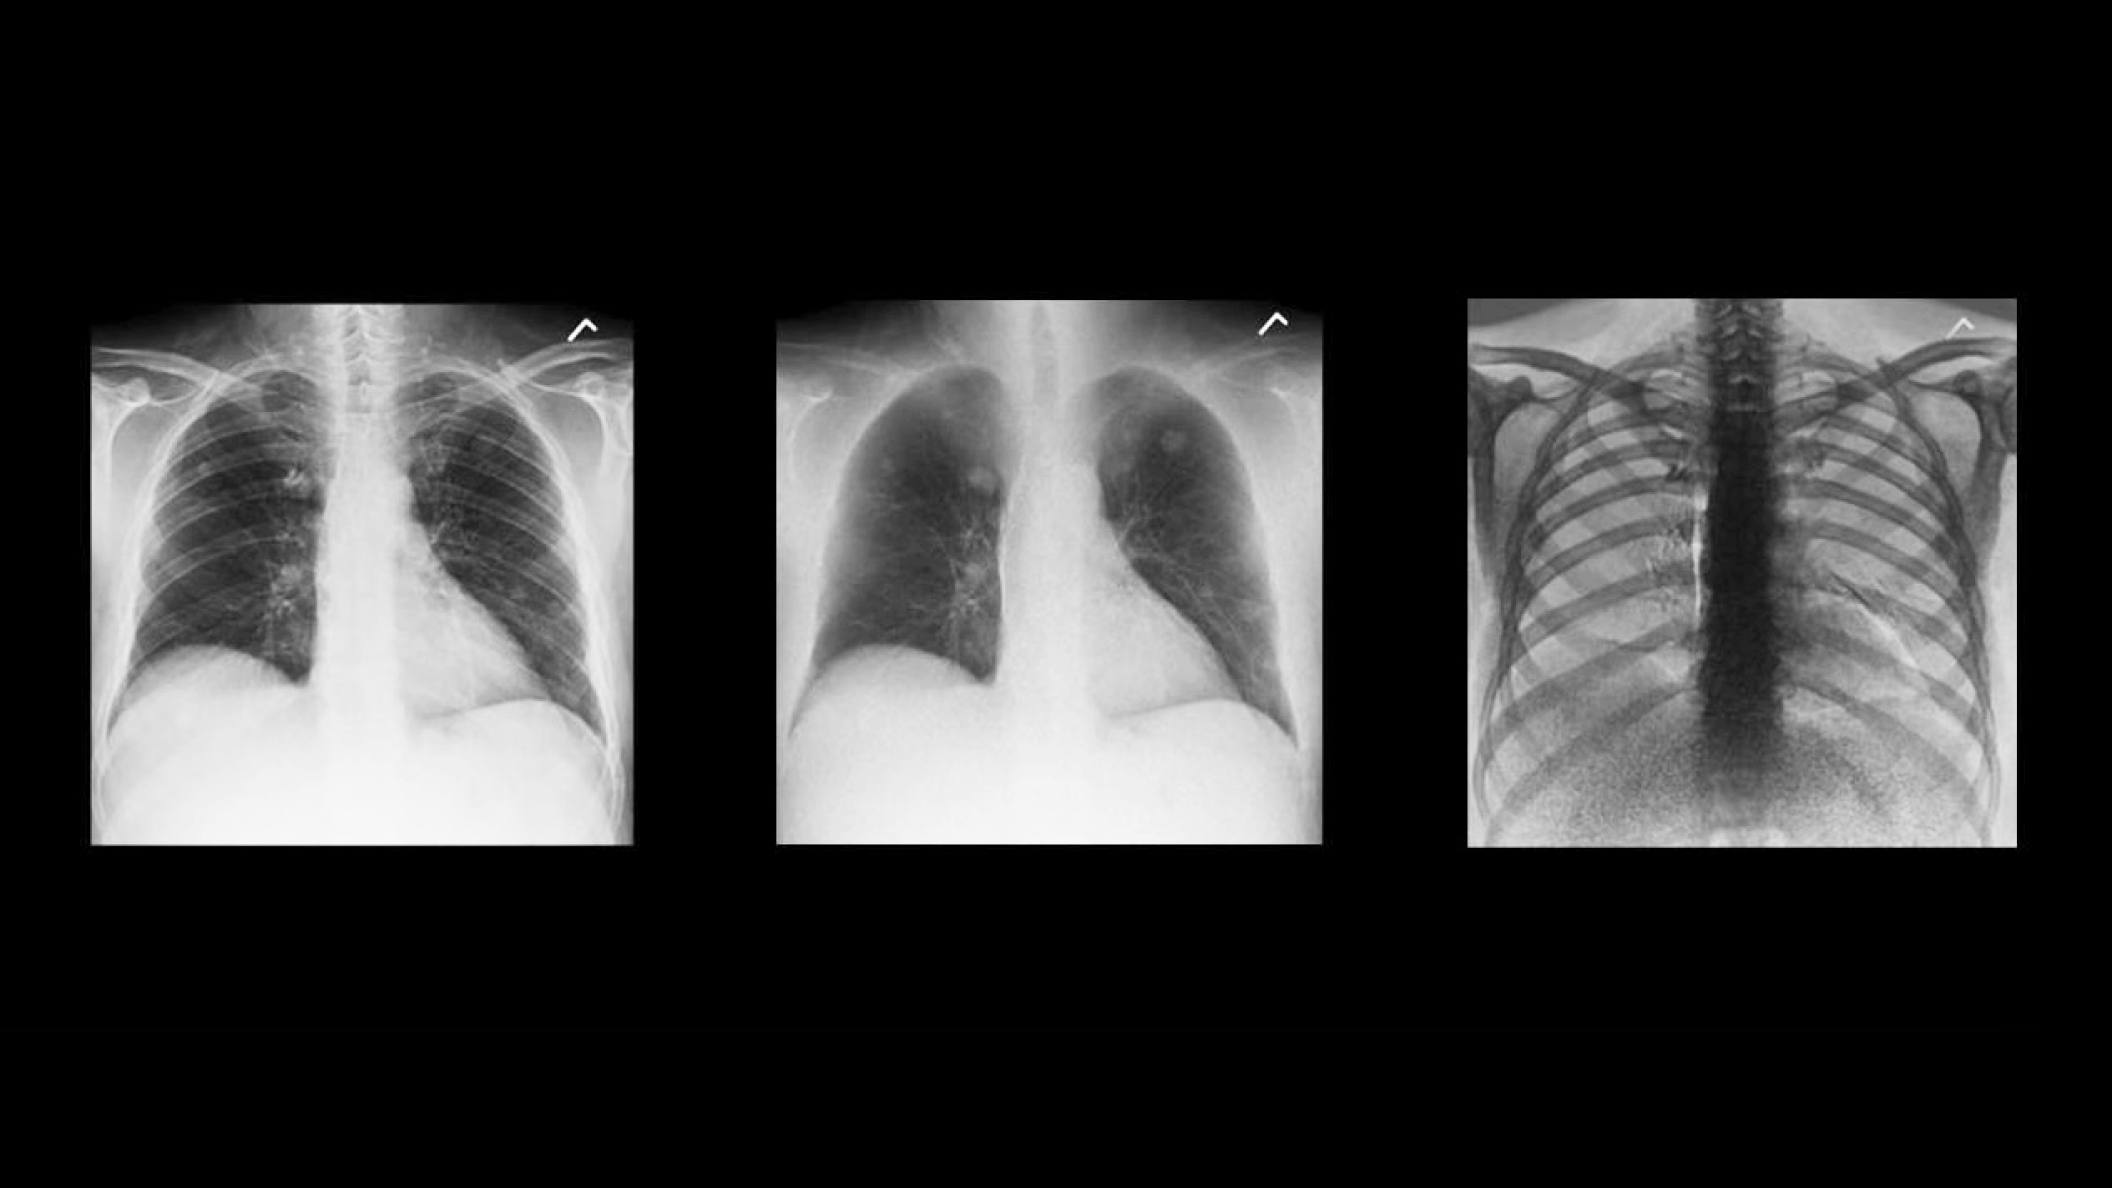

Rather than relying solely on algorithmic image processing, Dual Energy Subtraction acquires two exposures at different energy levels in less than 160 milliseconds. You can process and view the image as:

• A standard radiographic image

• An image with bones subtracted

• An image of just the bones to highlight foreign objects or calcified structures

These images help you detect abnormalities that may have been obscured in a conventional radiograph.